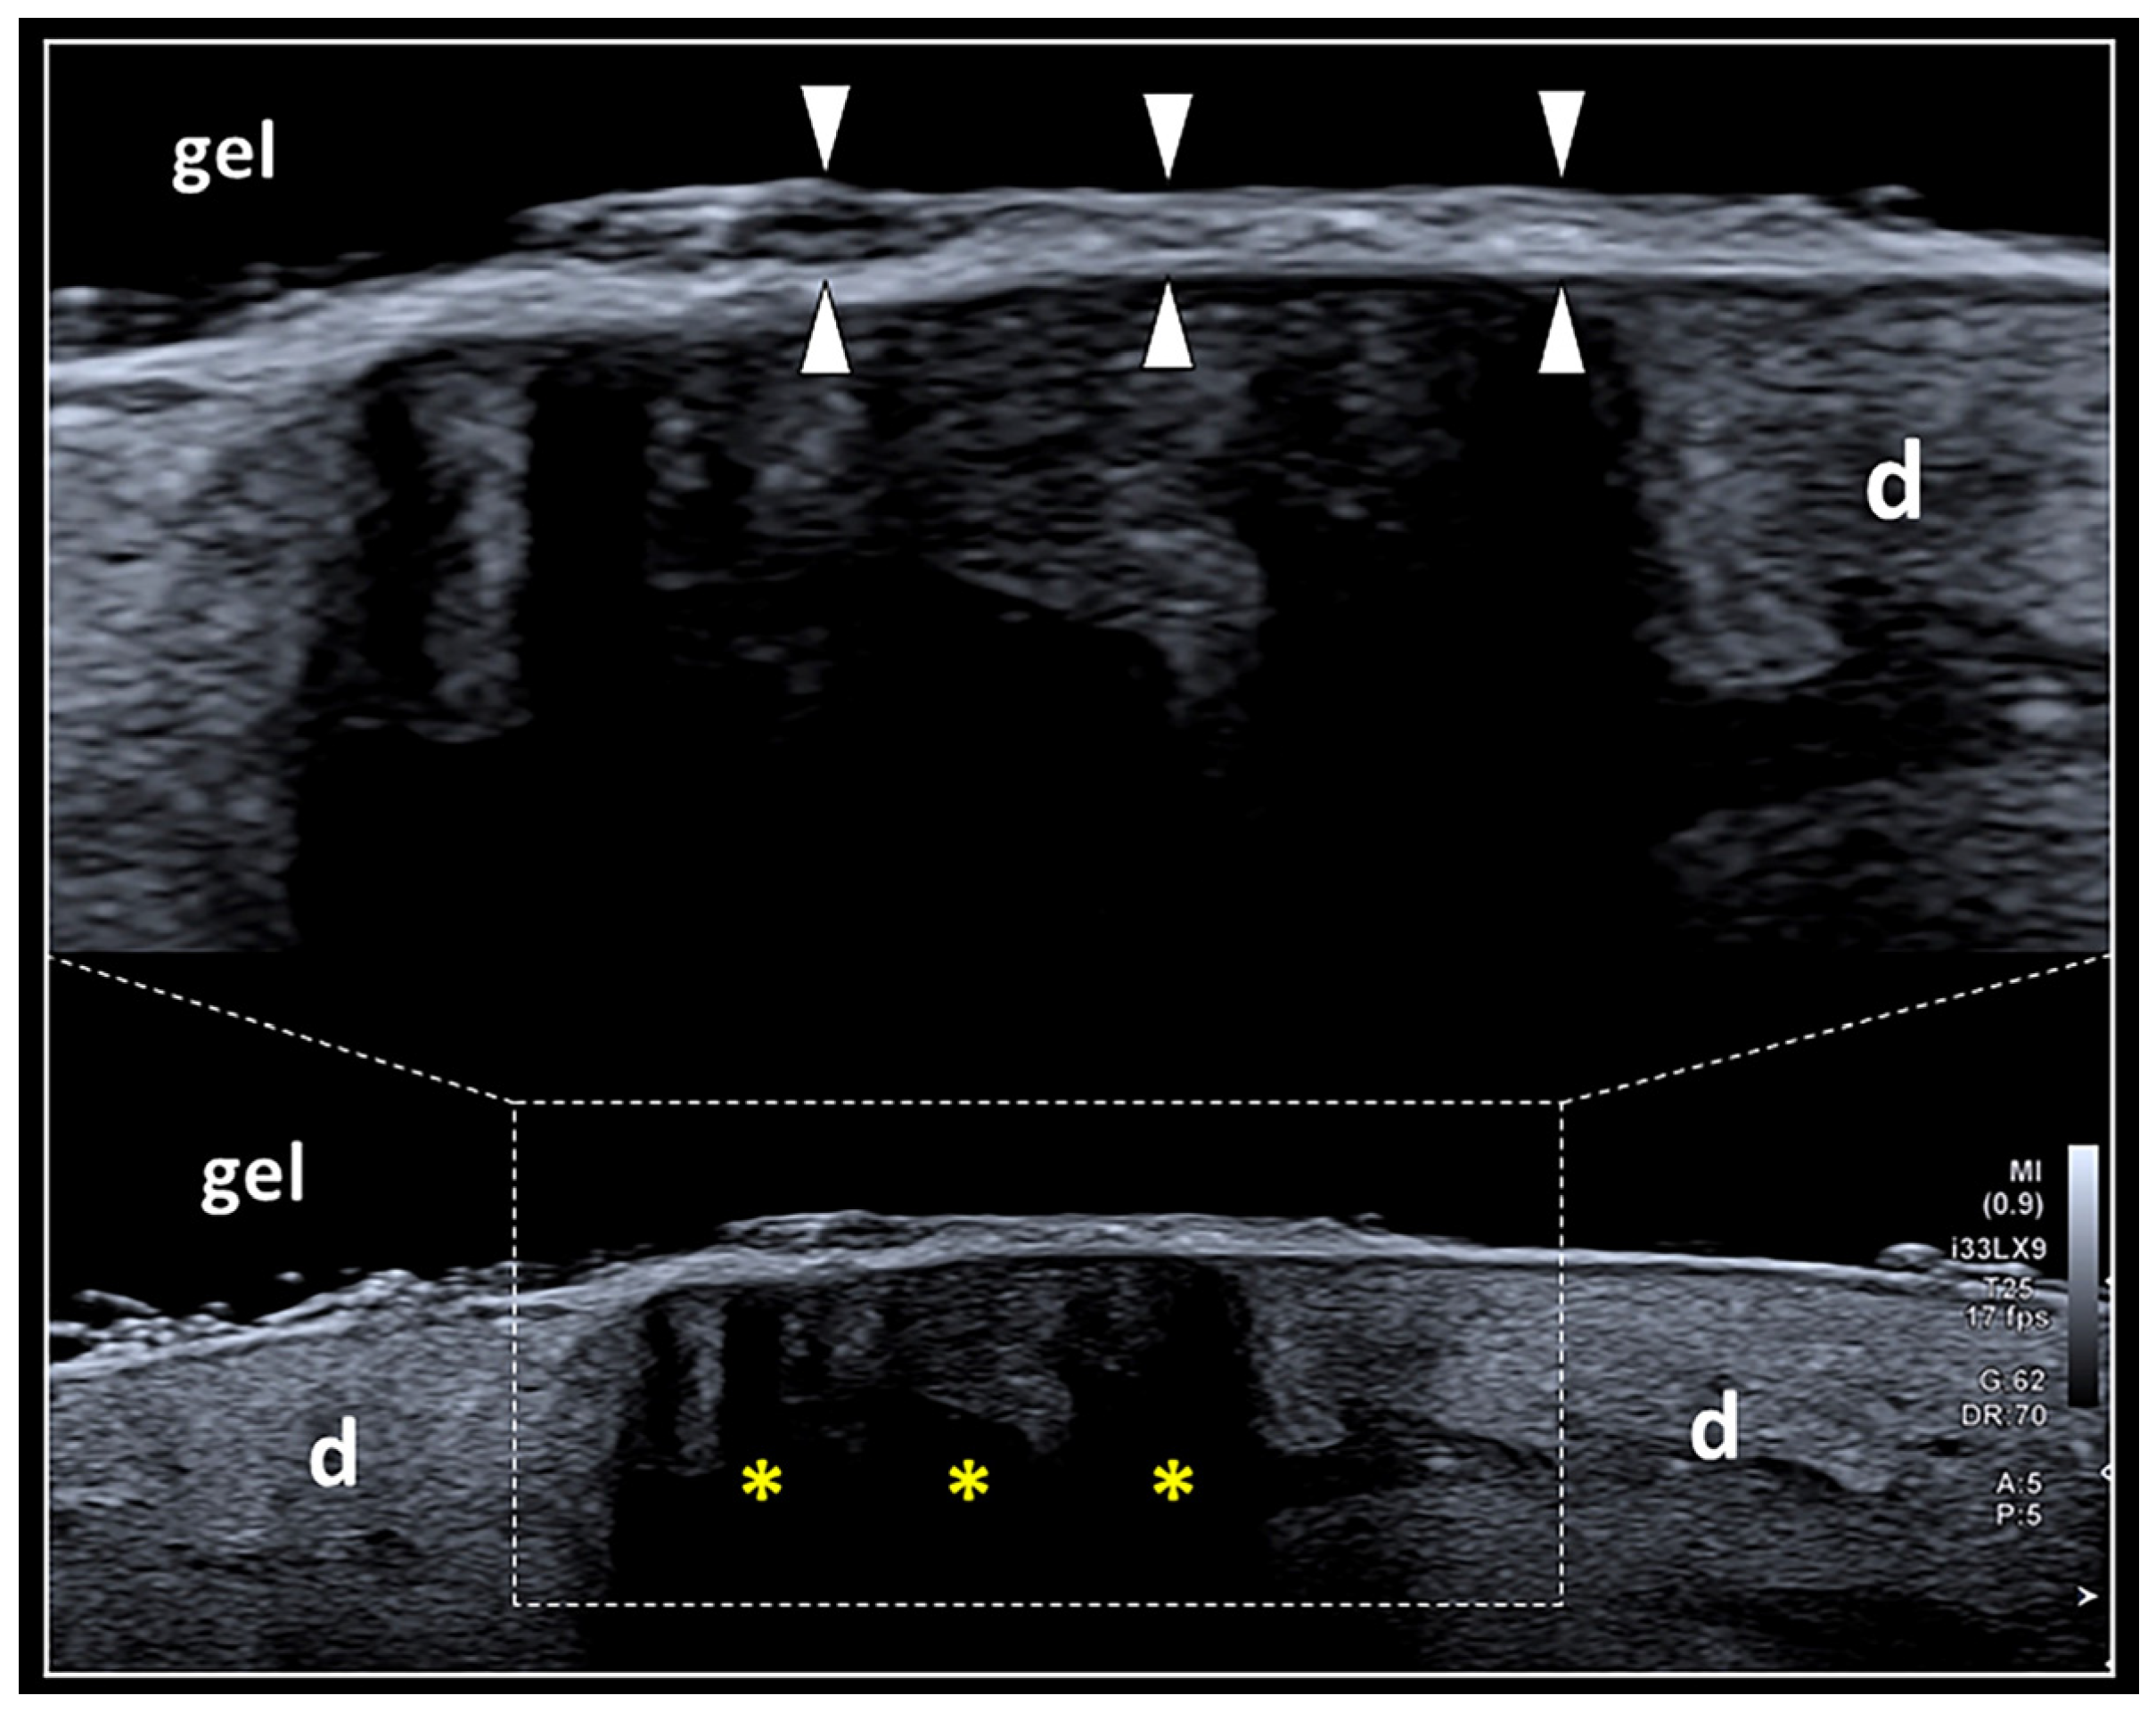

Figure 3.

The “deep masking effect”. Massive deposition of keratin laminae over the surface of the epidermis (white arrowheads) may generate a hyper-reflective interface reducing the penetration of the US beam within the deep layers and with the development of dark shadows (yellow asterisks) that mask the inner echotexture of the dermis (d). The “deep masking effect” can be physically considered very similar to the artifact of partial acoustic shadowing.